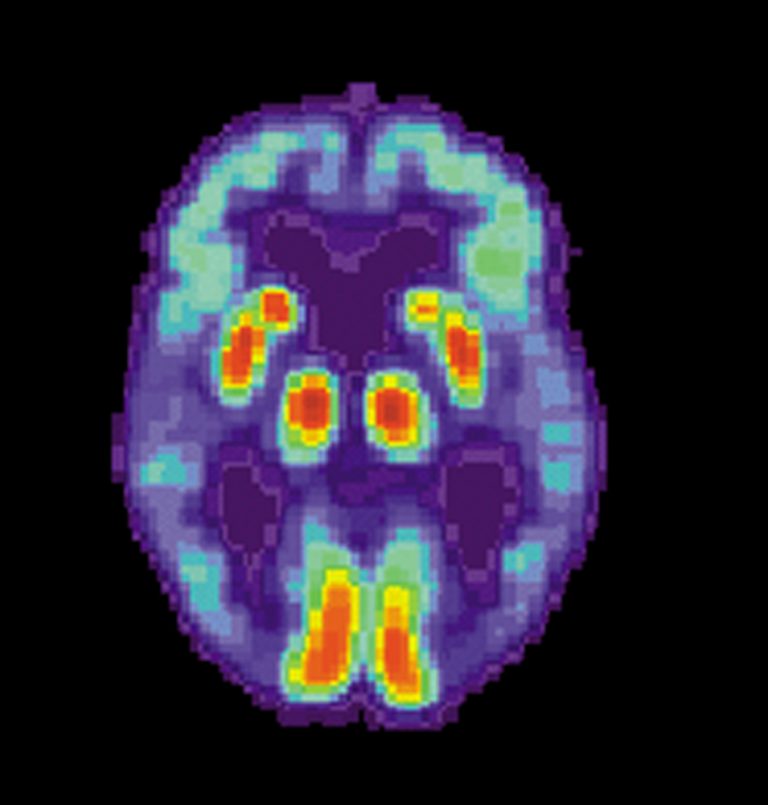

A new study by scientists in Australia and the US provides an explanation for why clinical trials of drugs targeting proteins in the brain that were thought to cause dementia and Alzheimer’s have failed. The study has opened the way for potential new treatments with existing drugs.